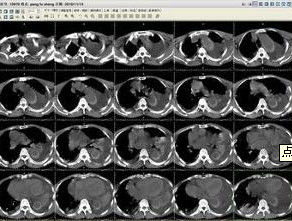

主動脈夾層動脈瘤(二)X線 胸部平片見上縱隔或主動脈弓影增大,主動脈外形不規則,有局部隆起。如見主動脈內膜鈣化影,可準確測量主動脈壁的厚度。正常在2~3mm,增到10mm時則提示夾層分離可能性,若超過10mm則可肯定為本病。主動脈造影可以顯示裂口的部位,明確分支和主動脈瓣受累情況,估測主動脈瓣關閉不全的嚴重程度。缺點是它屬於有創性檢查,術中有一定危險性。CT可顯示病變的主動脈擴張。發現主動脈內膜鈣化優於X線平片,如果鈣化內膜向中央移位則提示主動脈夾層,如向外圍移位提示單純主動脈瘤。此外CT還可顯示由於主動脈內膜撕裂所致內膜瓣,此瓣將主動脈夾層分為真腔和假腔。CT對降主動脈夾層分離準確性高,主動脈升、弓段由於動脈扭曲,可產生假陽性或假陰性。但CT對確定裂口部位及主動脈分支血管的情況有困難,且不能估測主動脈瓣關閉不全的存在。

(四)磁共振成像(MRI) MRI能直接顯示主動脈夾層的真假腔,清楚顯示內膜撕裂的位置和剝離的內膜片或血栓。能確定夾層的範圍和分型,以及與主動脈分支的關係。但其不足是費用高,不能直接檢測主動脈瓣關閉不全,不能用於裝有起搏器和帶有人工關節、鋼針等金屬物的病人。